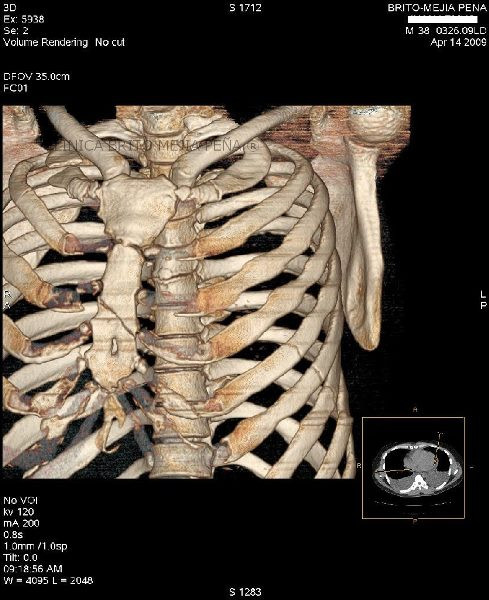

Fracturas costales

Fracturas en esternón y costillas